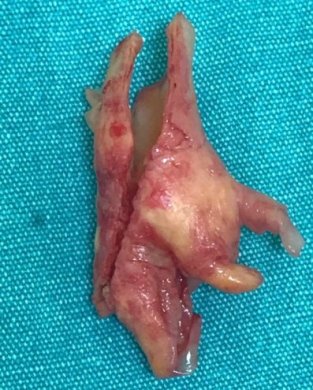

Boyuna karotis damar üzerindeki cildin 5cm'lik kısmına lokal anestezi uygulanır. Daha sonra 4-5cm'lil kesiden damara ulaşılır. Damar duvarı açılır ve damar içerisindeki plak çıkartılarak damar direk veya yama konularak kapatılır. Ortalama operasyon süresi 1.5-2 saat civarındadır.

Resim 1,2. Karotis endarterektomi (Karotis damar içerisinden plak çıkarımı)